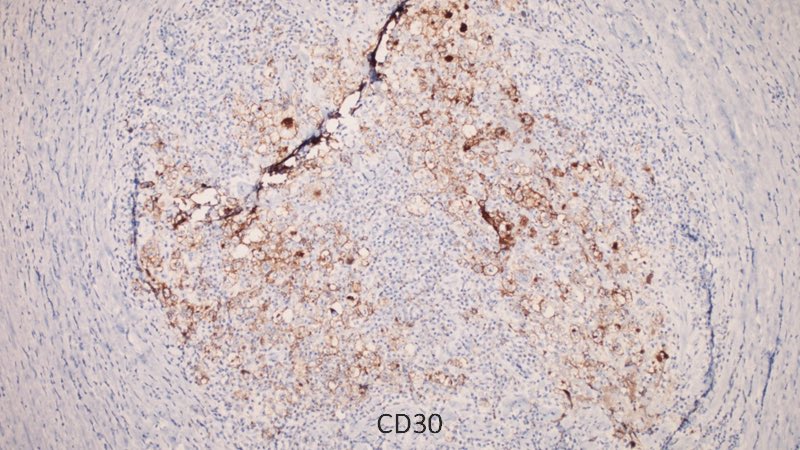

Pre-auricular nodule x 1month from 31yo patient, no other complaint. #pathtwitter #surgpath #ENTpath #hemepath #pathboards Einstein Montefiore Pathology Ridin Balakrishnan, MD Hansini Laharwani Siba El Hussein, MD Mitul B. Modi, MD Tristan Rutland MBBS FRCPA IFCAP Jerad Gardner, MD Kamran Mirza MD PhD - کامران مرزا

63/male with abdominal lymphadenopathy. DQ gave the initial clue to hemepath diagnosis. Positive CD3/5/7/25. CD30 diffuse, ALK1/CD20 negative. CD30+ Mature T-cell lymphoma. D/D ALCL or ATLL HTLV1 is positive! #cyto #hemepath #PathTwitter Kevin Kuan Yanhua Wang #bridgingcytoheme